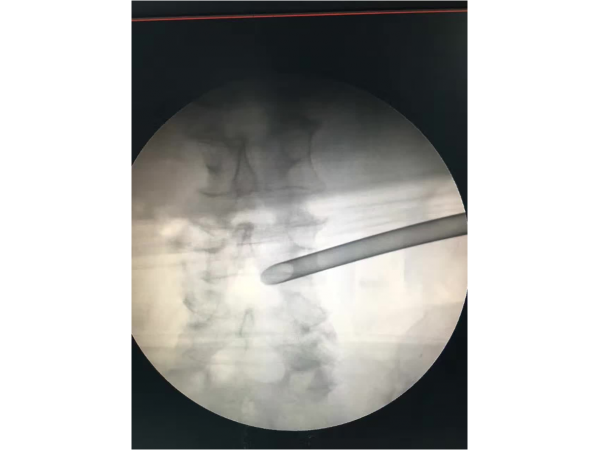

產(chǎn)品說明:椎間孔鏡手術(shù)步驟 : 步:手術(shù)前準(zhǔn)備 需要拍矢狀位和橫斷面的MRI確定突出的性質(zhì)。拍側(cè)面的X片確定椎間孔的大小和髂脊的高度。如

產(chǎn)品說明:1.手術(shù)體位:體位可以采用俯臥位和側(cè)臥位,我們習(xí)慣于采用俯臥位來完成PELD手術(shù)。2.畫線:先畫出腰椎棘突的連線,再畫出雙側(cè)髂嵴